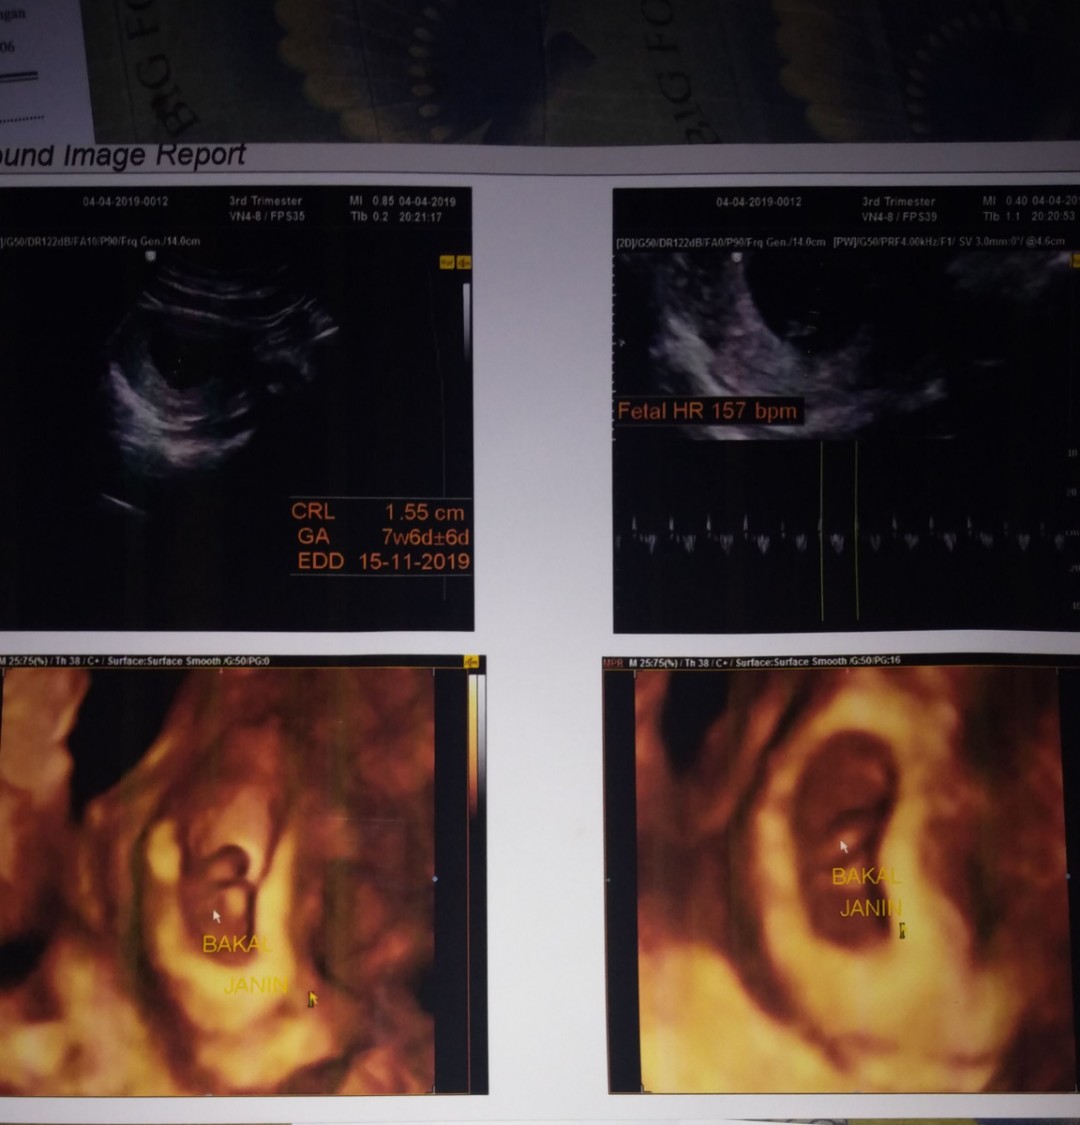

USG

Bund saya mau curhat , Kemaren saya Usg tpi cma keliahatan kantung rahim nya doang , janin nya gk kelihatan , saya sampai bengong dokter bilang begitu , ko bisa janin nya gk keliatan ? perkiraan bidan usia kandungan saya sdh 11 minggu tpi kemaren kta dokter kemaren baru 8 minggu bun, pertanyaan saya bunda Apakah Normal usia kandungan 8 minggu di USG blm keliatan janin nya ? tolong kasih pemasukan bunda saya sampai kepikiran trs dan takut jga ? trimakasih bnyak sebelum nya .